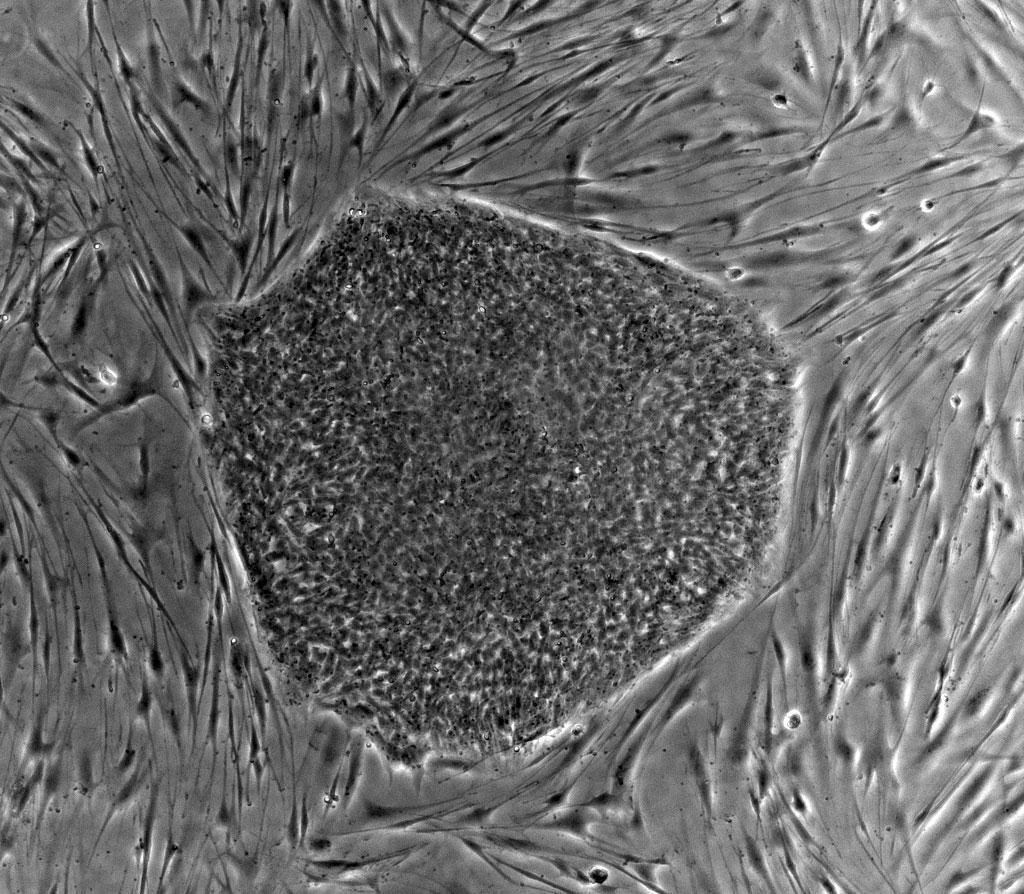

在這項研究裏,研究人員系統地呈現了人體中的兩種代表性細胞——分化能力極強的人類胚胎幹細胞,以及到達了分化終點,完全成型了的成纖維細胞中的染色體三維結構。

人類胚胎幹細胞(中央)和餵養它們的小鼠胚胎成纖維細胞(外周),這兩種細胞的形態、結構有着巨大的差異 | wikipedia commons